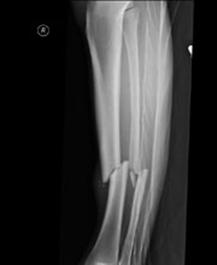

Fracturi simple: SPIRALA OBLICA TRANSVERSALA

Fractura spirala de Fractura transversa de diafiza femurala Fractura spirala de diafiza tibiala

diafiza humerala

Fractura spirala de diafiza tibiala Fractura oblica de diafiza tibiala Fractura transversala de diafiza tibiala